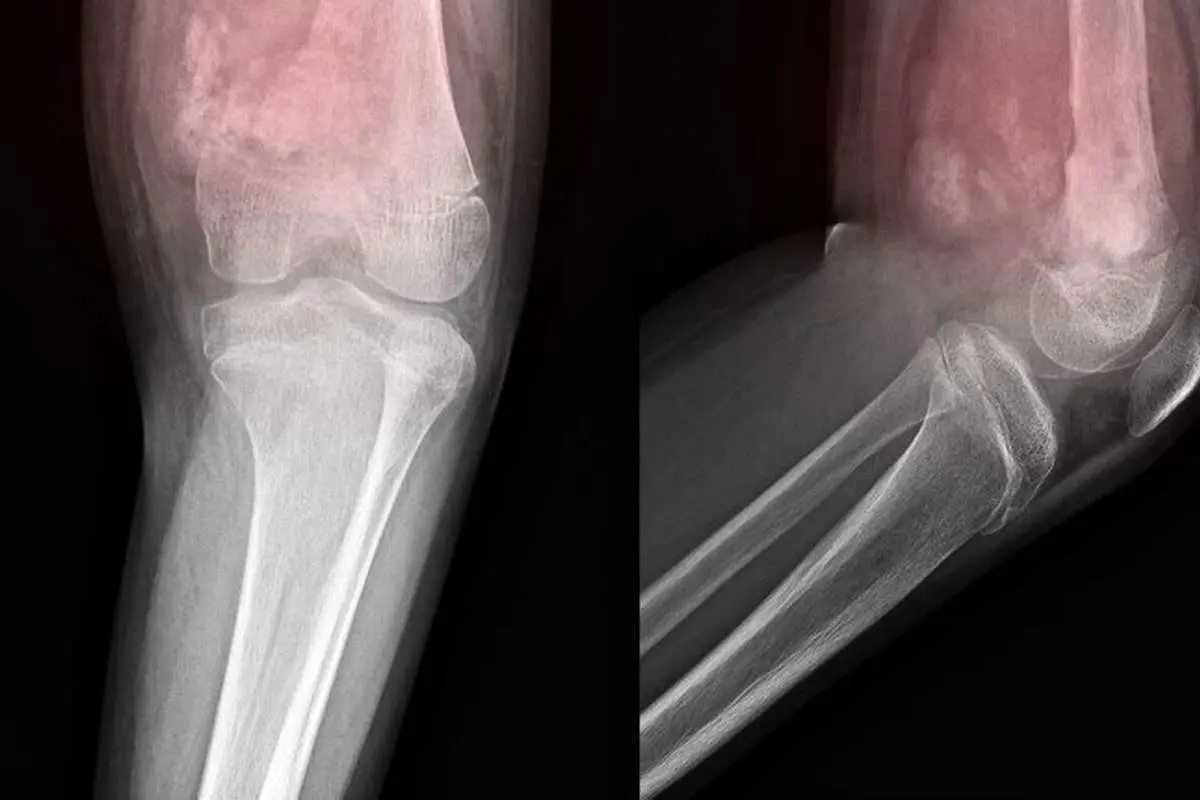

سرطان استخوان می‌تواند هر استخوانی را درگیر کند، اما در بیشتر موارد در استخوان‌های بلند پا‌ها و بازو‌ها ایجاد می‌شود.

علائم اصلی آن شامل درد مداوم استخوانی که بدتر می‌شود، تورم و قرمزی روی استخوان، توده قابل‌توجه روی استخوان، استخوانی که راحت‌تر از حد طبیعی می‌شکند یا ترک می‌خورد و همچنین مشکل هنگام حرکت است.

شایع‌ترین نوع سرطان استخوان به نام «استئوسارکوم»، بیشتر کودکان و جوانان زیر ۲۰ سال را درگیر می‌کند.